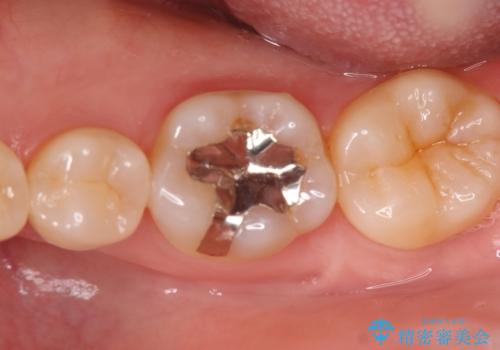

銀歯の下の虫歯|オールセラミッククラウン

担当医 河野豊嘉